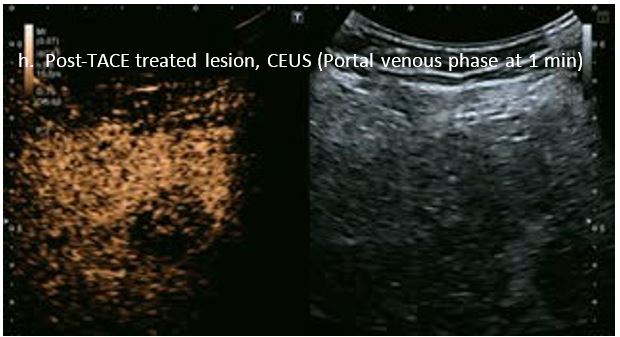

Оцінка результатів лікування ГЦК

Проведено повторне обстеження 79-річного чоловіка з цирозом печінки В, ускладненим ГЦК, після транс-артеріальної хіміоемболізації (ТАХЕ). Було виявлено нове ураження, розташоване поруч з ураженням після ТАХЕ. На сірошкальному зображенні чітко видно нове ураження, але складно виявити рецидив ГЦК в зоні ураження після ТАХЕ. За допомогою кольорового картування SMI (cSMI) можна побачити розвинену судинну мережу всередині нового вогнища ураження. Для оцінки результату лікування було виконано CEUS. За допомогою CEUS можна легко дослідити як нове ураження, так і рецидив ГЦК у вогнищі ураження після TACE. Нове ураження демонструє гіперпосилення артеріальної фази і відсутність вимивання до 5 хвилин, отже, це ураження LI-RADS 4, ймовірна ГЦК за критеріями LI-RADS. Підживлюючі судини можна чітко спостерігати в ранній артеріальній фазі. Для ураження після TACE, більша його частина не підсилюється, однак, в артеріальній фазі спостерігається ділянка гіперпосилення у верхній частині лікованого ураження, що вказує на рецидив ГЦК.

Малюнок 10